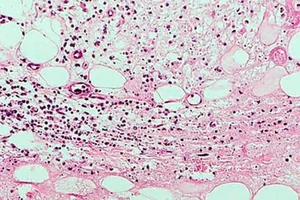

Úc đau đầu với đại dịch “loét ăn thịt” ngày một lan rộng